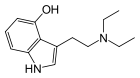

| 5-HO-DET | artificial | 5-OH | CH2CH3 | CH2CH3 | 5-hydroxy-N,N-diethyltryptamine | 14009-42-8 |